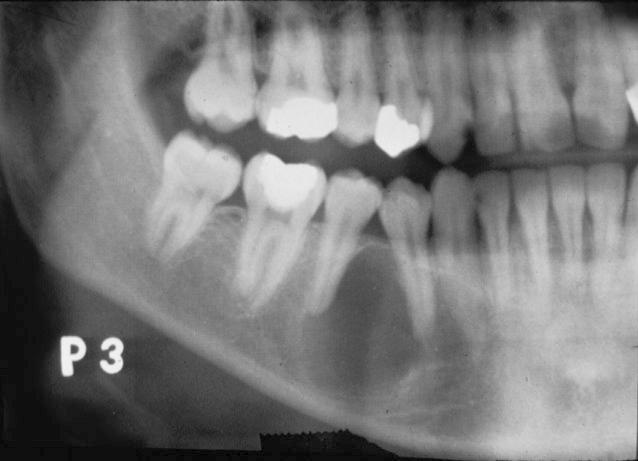

Idiopathic osteosclerosis XRAY manifestations

Well defined - Round or Elliptical

Radiopaque

Usually associated with root apex

NO radiolucent rim

Idiopathic osteosclerosis

Healthy tooth

Radioopaque

Well defined